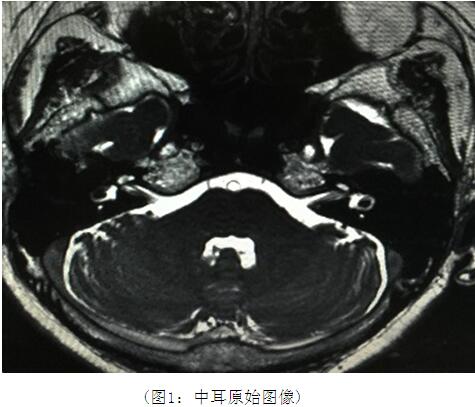

1.全部病例均获得满意的MR影像。其6例患者半规管连续中断伴畸形,面、听神经有不同程度的病变,24例患者未见异常。原始数据图因没有上下结构的重叠而显示尤为清晰(图1)。